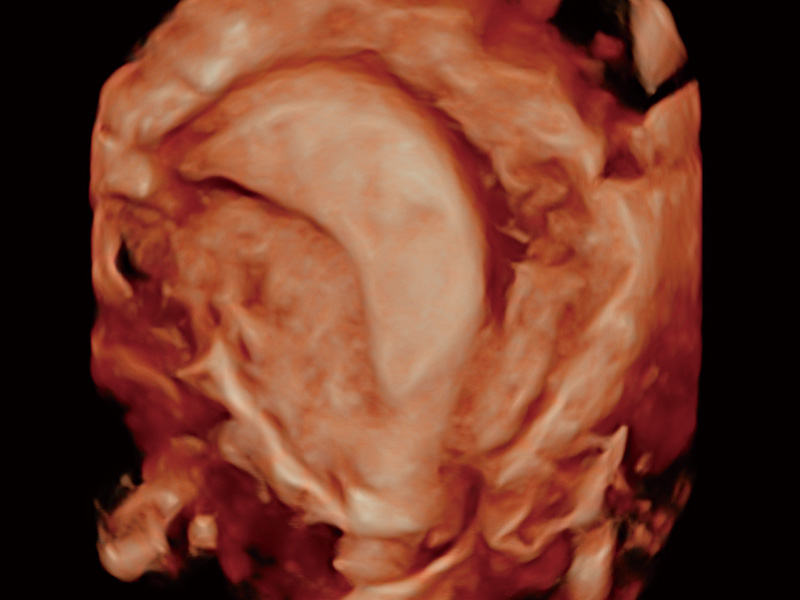

单角子宫